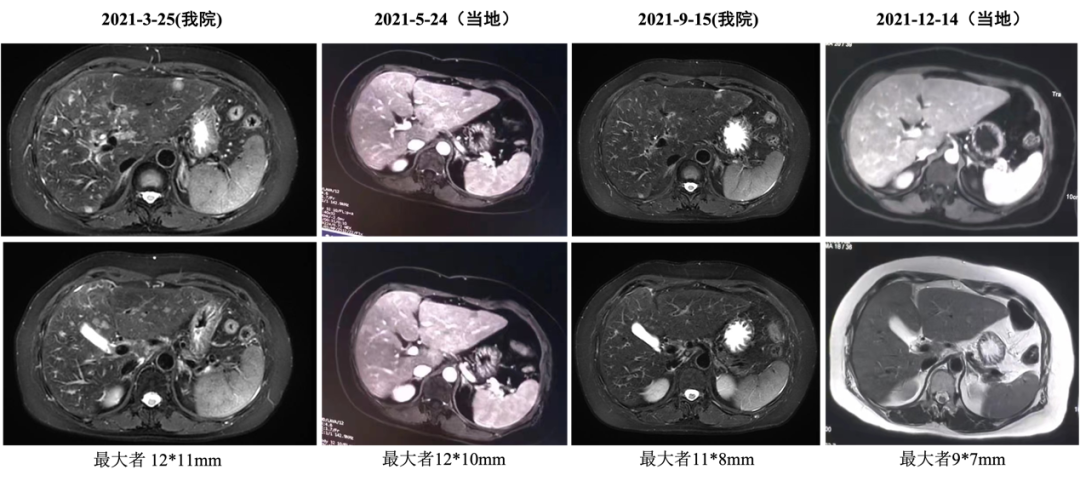

2020-12-22始行吉西他滨+曲妥珠单抗(汉曲优)+帕妥珠单抗治疗,具体:吉西他滨1g/m2 1.6g d1、1.8g d8;曲妥珠单抗首次 8mg/kg 520mg,以后6mg/kg 390mg,帕妥珠单抗首次840mg,以后420mg,d1,Q21d;自第10周期开始双靶维持治疗。2021-03-25复查:肝内多发转移较前减少、缩小(较大24x20mm→12x11mm),肝门区及门腔间隙淋巴结缩小(28*18mm→12*7mm),左侧肋骨转移减轻),最佳评效PR。2021-12-15头MRI示可疑脑膜转移,评效PD,PFS为12月。不良反应:手足麻木2度,肝功损伤2度。

图7 六线治疗